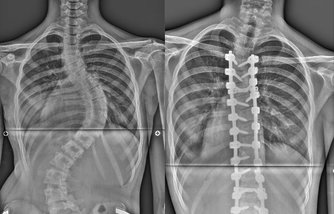

V posledních letech byl v oblasti páteřní chirurgie učiněn významný pokrok. Pracoviště využívá všech nových technologií, které umožňují provádět jak jednoduché, tak i složité operace na páteři. Na pracovišti jsou ošetřováni hlavně pacienti s degenerativním onemocněním, dále to jsou rozlišné deformity páteře následkem úrazu či získané deformity, akutní traumata, nádorová onemocnění, osteoporóza a jiná onemocnění. Oddělení se specializuje na problematiku skolióz a mininvazivní operační přístupy. Jedná se tedy o celé spektrum moderní spondylochirurgie, kromě traumat s míšní lézí. Za rok odoperuje cca 300 páteřních výkonů.

Operace skoliosy je náročný chirurgický výkon, který ovlivní celý organismus pacienta. Pro obnovení funkce pohybového aparátu musí pacient dodržovat doporučení daná operatérem a fyzioterapeutem. Preferujeme individuální přístup ke každému pacientovi, ale pro lepší orientaci a zapamatování mohou pomoci tyto pokyny a stručný nárys cvičební jednotky.